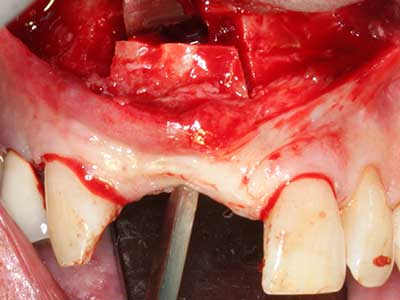

Bone tissue is not simply a mineral structure but also contains a substantial proportion of collagen fibres. This means it not only has good compressive strength but also a degree of flexibility, which can be taken advantage of when performing bone augmentations. In the classical expansion procedure using bone splitting, the atrophied alveolar ridge is split longitudinally and carefully expanded after reaching an adequate osteotomy depth (Fig. 13-16), ideally without substantial removal of the periosteum (Brugnami, Caiazzo et al. 2014, Stricker, Fleiner et al. 2014). Screw and plate systems with increasing expansion distance have proven effective in separating the two bone lamellae while remaining below the fracture threshold. In general, residual bone widths of at least 3–4 mm are required (Chiapasco, Zaniboni et al. 2006) to guarantee adequate flexibility and sufficient bone coverage of the future implants. If necessary, a vertical relief osteotomy on one or both sides can improve flexibility. A combination with additional augmentation techniques, particularly on the buccal side, has been described as an alternative to the classical technique.

The splitting procedure is particularly atraumatic and there is no significant loss of dimension when using piezosaws, and there are no significant differences between implants in split jaws and implants in an alveolar ridge without a bone deficit (Chiapasco, Zaniboni et al. 2006, Danza, Guidi et al. 2009). However, sufficient continuous irrigation is essential, particularly with locally restricted and deep splitting to prevent thermal stress in the apical osteotomy regions.